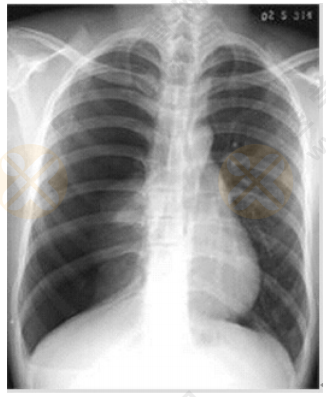

中医助理医师实践技能【西医临床答辩】02号题:根据下图所给X线片分析临床意义

根据下图所给X线片分析临床意义。(5分)